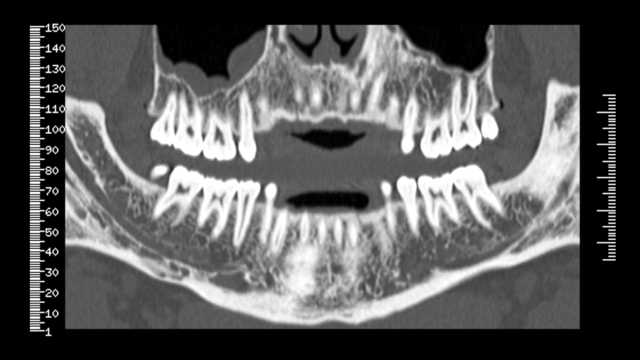

Tomógrafo de Haz Cónico (TCHC –Tomógrafo Computerizado de Haz Cónico–, o CBCT –Cone Beam Computed Tomography–), que se introdujo en 1997-1999 en Europa, con el NewTom,

*Radiología Digital Tridimensional.

Inundándose todo el sector dental con otros productos de los demás fabricantes (i-CAT-ISI, CB-Mercuary-Hitachi, 3D-Accuitomo-JMorita, Picasso-Vatech-Ewoo, Iluma-Kodak, Galileos-Sirona, Planmeca,etc.).